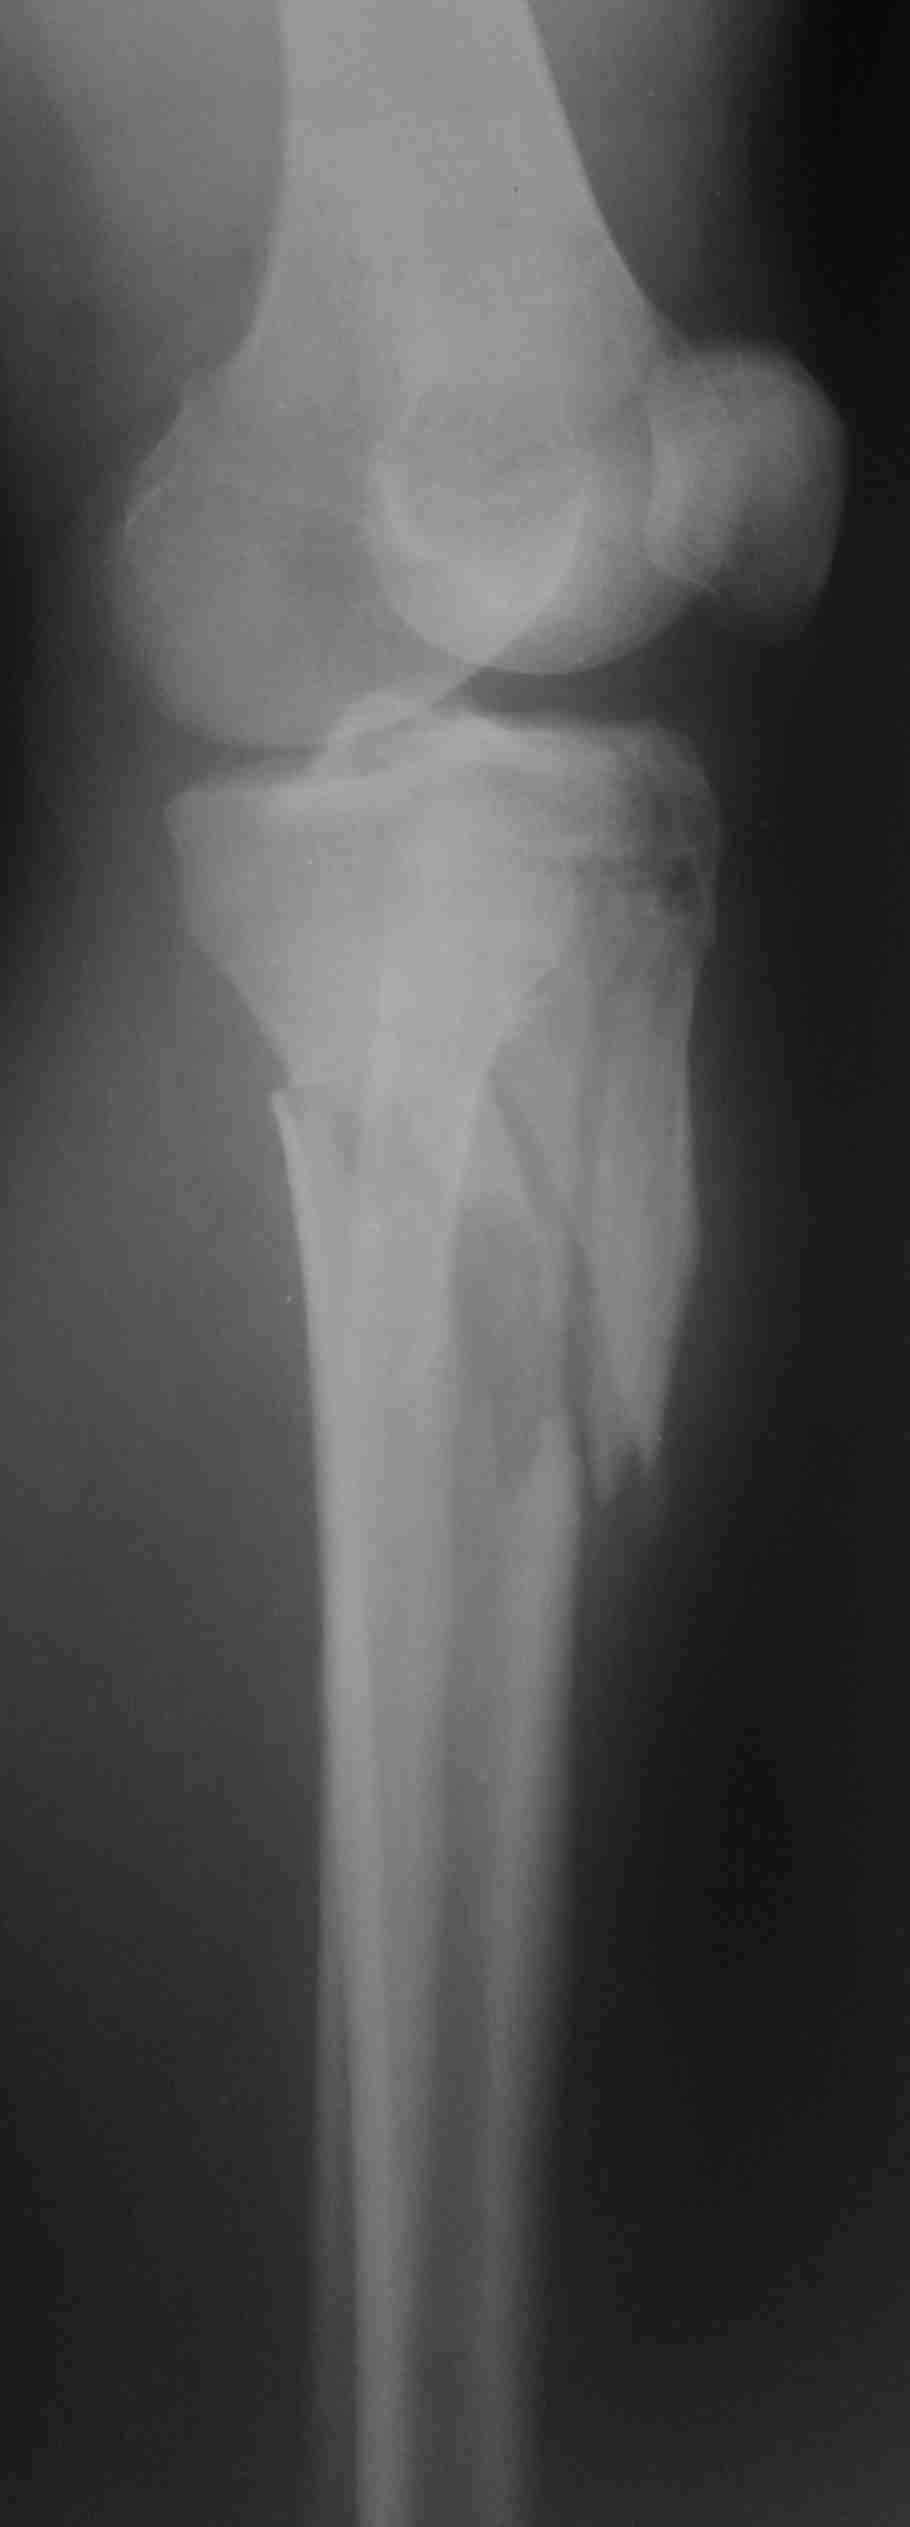

Re: Перелом верхней трети костей голени

послал Maxim Agalakov 11 Январь 2013, 11:27

Похожий случай, вчера прооперировали. Непрямая репозиция, малоинвазивный остеосинтез без обнажения зоны перелома.